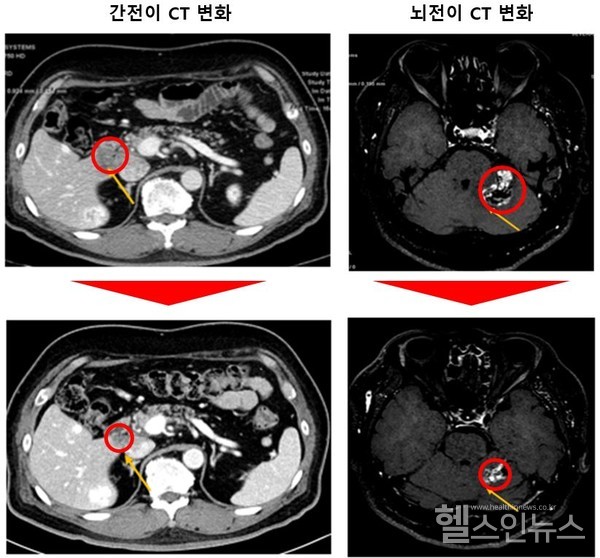

같은 연구팀이 동물을 대상으로 진행한 전임상 시험에서도 좋은 성적을 확인할 수 있었다. KRAS G12C 돌연변이 비소세포폐암 환자와 소토라십 치료를 받고 내성을 보이는 환자 종양을 마우스에 이식한 실험에서 우수한 효과를 나타냈다. 나아가 뇌전이까지 나타난 마우스도 뇌종양 감소를 보였다.